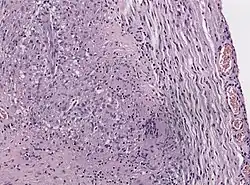

Granulomatous inflammations.

The cause of Tolosa–Hunt syndrome is not known. The disorder is thought to be, and often assumed to be, associated with inflammation of the areas behind the eyes (cavernous sinus and superior orbital fissure).[8] These granulomatous inflammations involve lymphocytes, plasma cells, and multinucleate giant cells. Clinical cases have shown that the disorder consists of the inflammation of multiple cranial nerves, with the highest prevalence of ocular motor nerves. In some cases, it also involves the inflammation of sensory nerves, specifically the trigeminal nerves.